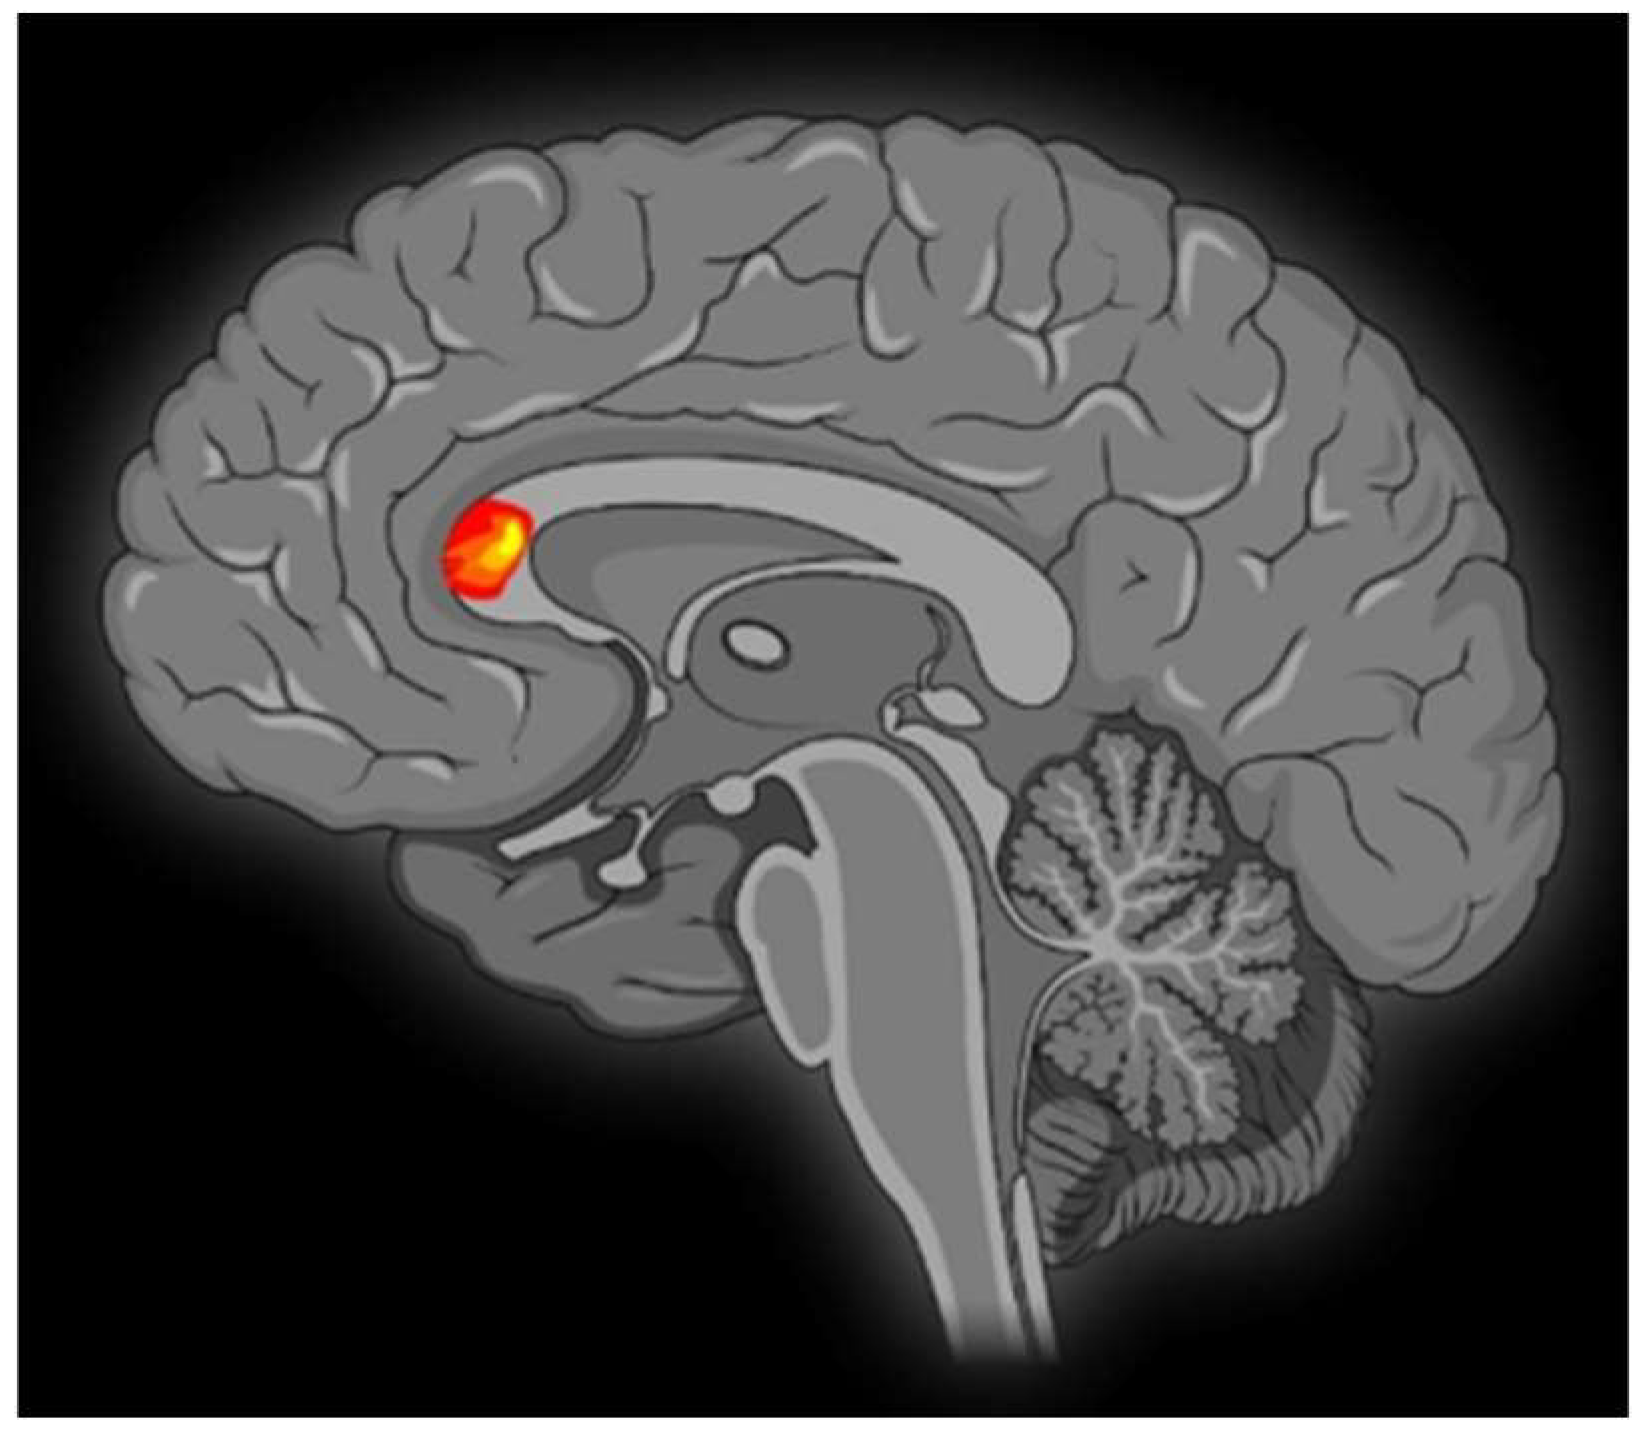

Contrasting minor with major melodies showed multiple activation sites (Figure 1) with the right parahippocampal gyrus (RPHG) being an eloquent brain area (Figure 2). Another discernible activation, when subjected to cluster-level correction, spanned both the left and right ventral anterior cingulate cortex (VACC) (BA 24) and extended into the left medial frontal gyrus (LMFG) within the medial prefrontal cortex (BA 10) (Figure 3). Remarkably, the inverse contrast (major over minor) did not yield significant activations. In a peak-voxel analysis, the response to the chromatic scale was intermediary when juxtaposed against the major and minor mode melodies for three of the aforementioned regions. These differential responses between the chromatic scale and melodies were not statistically significant, with an exception. Within the LMFG, the chromatic scale evoked the most prominent (least negative) response, trailed by the minor and subsequently the major mode. Notably, the contrast between the chromatic scale and the major mode was statistically significant in this context [25].

VACC activation is generally associated with affective processing, while its dorsal counterpart is linked with cognitive functions [26]. Moreover, the existing literature indicates that the VACC displays heightened sensitivity to emotional content characterized by negativity or sadness [27]. The observed engagement of the VACC might be consistent with the perception of minor mode melodies as possessing a sadder tonality in comparison to major melodies. Notably, prior neuroimaging research on mode-based contrasts has not reported VACC activation in contrasts between minor and major modes [28].

The detected involvement of the left medial frontal gyrus (LMFG) may be attributed to its robust neural connectivity with the anterior cingulate cortex and other limbic systems. Such a connectivity profile underscores the proposed function of the medial prefrontal cortex as an integrative nexus for emotional input from these associated regions [29].